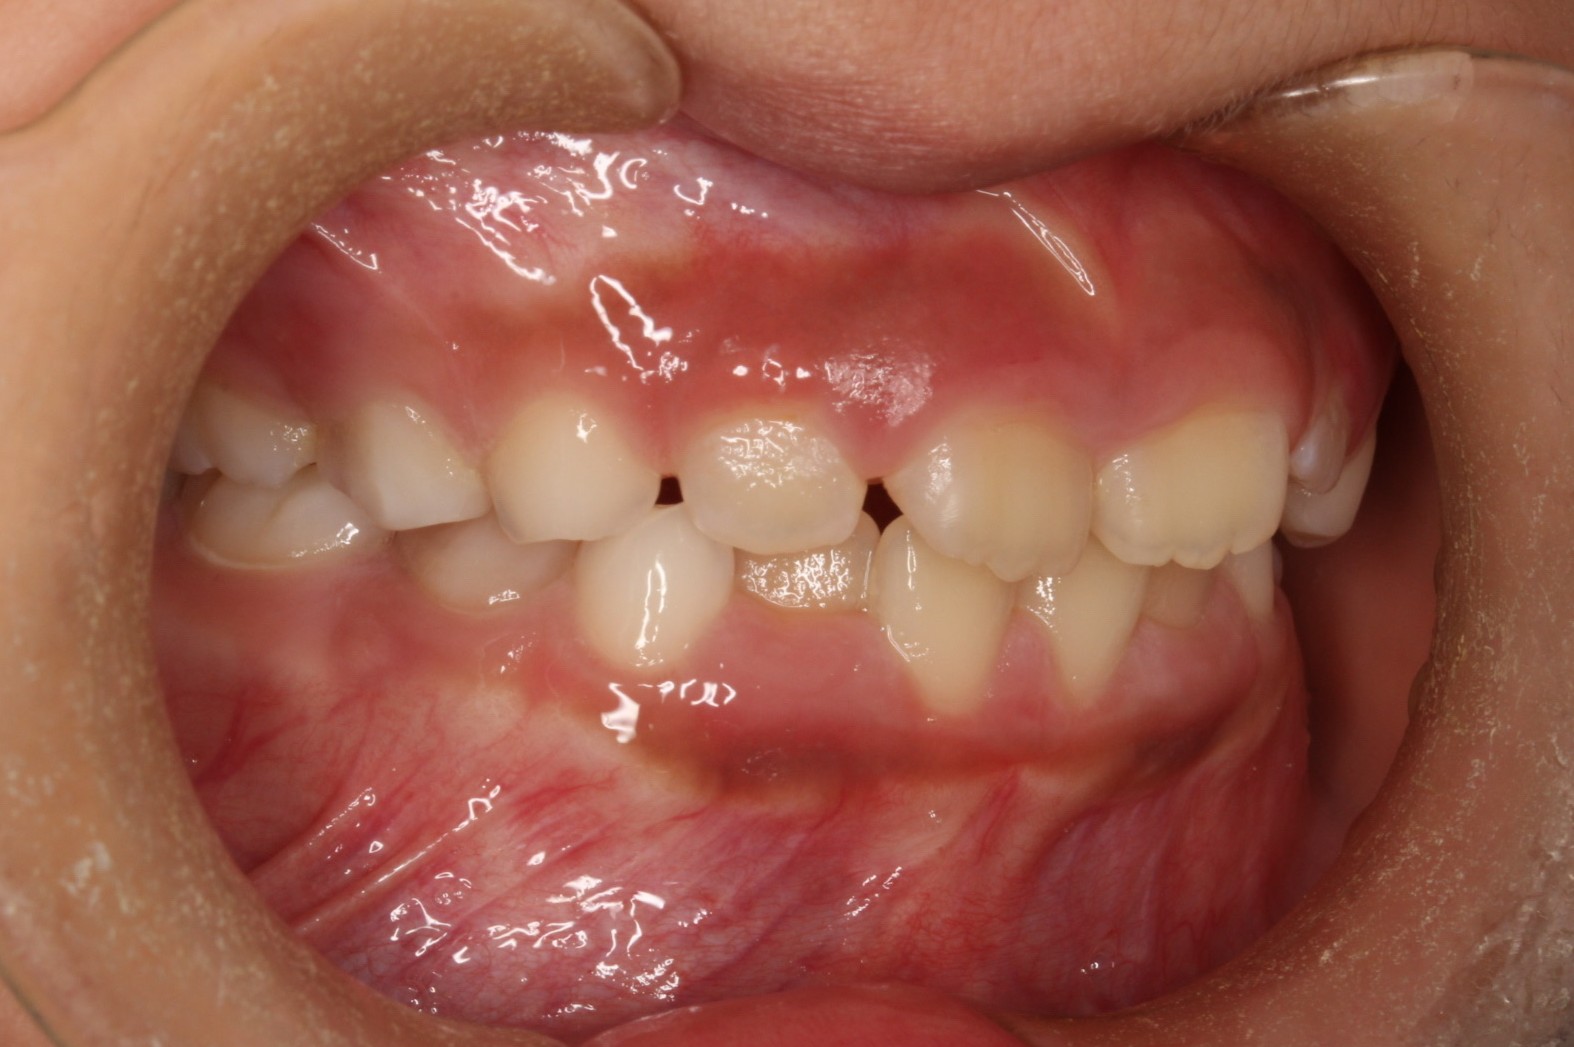

矯正術前:右側

矯正術前:左側